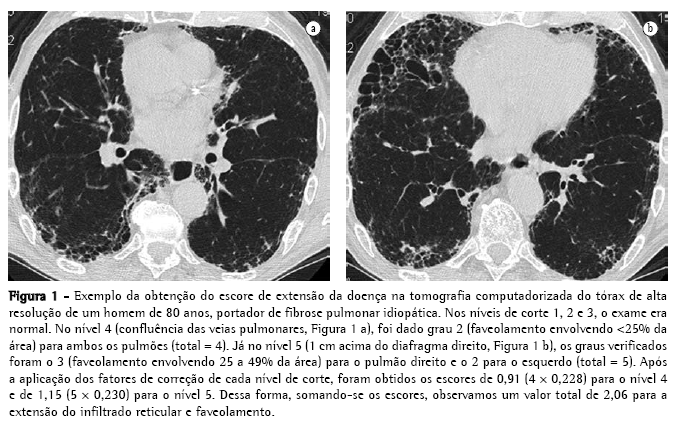

Ao final, somando-se os escores de cada nível, obteve-se os valores de Tot, Ret+Fav e Vif. Um exemplo da obtenção desses escores é mostrado na Figura 1.

FPI pela TCAR apenas mediante a concordância de todos os leitores e o preenchimento dos critérios clínicos e funcionais acima descritos. Inicialmente, a TCAR foi analisada de forma geral (sem considerar níveis de corte), procurando-se os seguintes achados: nódulos, opacidades em vidro fosco, infiltrado reticular, faveolamento (cistos <3 mm e >3 mm), bronquiectasias de tração, áreas de aprisionamento de ar e enfisema.(18,19) Posteriormente, a TCAR foi avaliada quanto à extensão e intensidade do envolvimento pulmonar intersticial, considerando-se cinco níveis de corte: 1) origem dos grandes vasos; 2) croça da aorta; 3) carina; 4) confluência das veias pulmonares; e 5) 1 cm acima do diafragma direito.(6,19-21) Através de um sistema de avaliação semiquantitativa, cada um desses níveis (direito e esquerdo, separadamente, totalizando 10 níveis) foi analisado quanto aos seguintes aspectos:

Escore de extensão do infiltrado reticular e faveolamento (Ret+Fav):

0) nenhum infiltrado reticular ou faveolamento;

1) infiltrado reticular sem nenhum faveolamento;

2) faveolamento (com ou sem infiltrado reticular) envolvendo <25% da área;

3) faveolamento envolvendo 25 a 49% da área;

4) faveolamento envolvendo 50 a 75% da área; e

5) faveolamento envolvendo >75% da área.(10,22,23)

Para a análise dos dados da TCAR, a estimativa do envolvimento pulmonar foi obtida mediante a aplicação de um fator de influência ('peso') para corrigir as diferenças dos volumes pulmonares em cada nível, conforme se segue(19):

origem dos grandes vasos - peso = 0,129;

croça da aorta - peso = 0,190;

carina - peso = 0,222;

confluência das veias pulmonares - peso = 0,228; e

1 cm acima do diafragma direito - peso = 0,230.